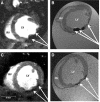

Basic and clinical studies have shown that bone marrow cell therapy can improve cardiac function following infarction. In experimental animals, reported stem cell-mediated changes range from no measurable improvement to the complete restoration of function. In the clinic, however, the average improvement in left ventricular ejection fraction is around 2% to 3%. A possible explanation for the discrepancy between basic and clinical results is that few basic studies have used the magnetic resonance (MR) imaging (MRI) methods that were used in clinical trials for measuring cardiac function. Consequently, we employed cine-MR to determine the effect of bone marrow stromal cells (BMSCs) on cardiac function in rats. Cultured rat BMSCs were characterized using flow cytometry and labeled with iron oxide particles and a fluorescent marker to allow in vivo cell tracking and ex vivo cell identification, respectively. Neither label affected in vitro cell proliferation or differentiation. Rat hearts were infarcted, and BMSCs or control media were injected into the infarct periphery (n = 34) or infused systemically (n = 30). MRI was used to measure cardiac morphology and function and to determine cell distribution for 10 wk after infarction and cell therapy. In vivo MRI, histology, and cell reisolation confirmed successful BMSC delivery and retention within the myocardium throughout the experiment. However, no significant improvement in any measure of cardiac function was observed at any time. We conclude that cultured BMSCs are not the optimal cell population to treat the infarcted heart.